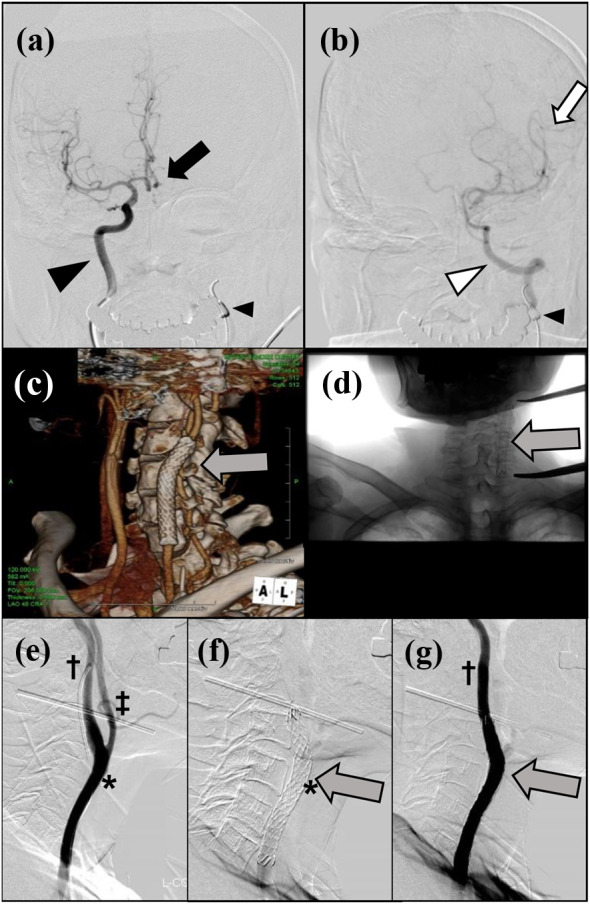

Given that CBS was considered imminent, we decided to attempt to prevent this by inserting an endovascular covered stent into the carotid artery. We considered that simultaneous surgical management of the recurrent tumor together with the carotid artery would then be a valid option. To assess the likely sequelae of sacrificing the carotid artery, we conducted both Matas and an Allcock tests to assess the cerebral circulation. A balloon catheter was used for internal carotid artery occlusion (Hyperform™, 7 × 7 mm, Medtronik, Carlsbad, CA, USA). No symptoms occurred during these tests. The left anterior cerebral artery was visualized via the right internal carotid artery (Fig. 2a) and the left middle cerebral artery via the left vertebral artery (Fig. 2b), the findings indicating that the circle of Willis was complete. An endovascular neurosurgeon then placed a covered stent (Niti-S Biliary Covered Stent, 8 mm × 6 cm; Century Medical, Shinagawa, Japan) endovascularly into the carotid artery without any complications (Fig. 2c–g). After determining the affected area of the carotid artery from the surface, a stent was inserted to reinforce the relevant area. The cranial side of the stent was located in the internal carotid artery, approximately 25 mm from the bifurcation of the common carotid artery (Fig. 2e, f). Angiography performed after expansion of the stent showed that adequate patency of the common and internal carotid arteries had been achieved and there was no leakage into the external carotid artery (Fig. 2g). Immediately prior to the balloon occlusion test and stent insertion, anticoagulation therapy was started. This comprised 5000 units of heparin intravenously, oral aspirin 200 mg, cilostazol 200 mg, and clopidogrel 300 mg as loading doses. From the day after stenting until 14 days before the scheduled surgery, the patient continued to receive cilostazol 100 mg and clopidogrel 75 mg orally daily.

Fig. 2.

Preoperative investigations. a Matas test: balloon occlusion of the left carotid artery (small arrowhead). The black arrowhead indicates the right carotid artery and the black arrow the left anterior cerebral artery visualized via the right internal carotid artery. b Alcock test: balloon occlusion of the left carotid artery (small arrowhead). The white arrowhead indicates the left vertebral artery and the white arrow the left middle cerebral artery visualized via the left vertebral artery. c Three-dimensional reconstructed CT image and d plain radiographic findings. The gray arrow indicates the endovascular covered stent. e Contrast image of the left common carotid artery just before insertion of a covered stent. *, assumed area of carotid artery involvement; †, internal and ‡, external carotid arteries. f A covered stent was inserted from the left common carotid artery to the left internal carotid artery (gray arrow). The distal end of the stent is approximately 25 mm cranial to the carotid bifurcation. g Carotid angiographic findings after stenting. The internal carotid artery is well visualized, whereas the external carotid artery is not